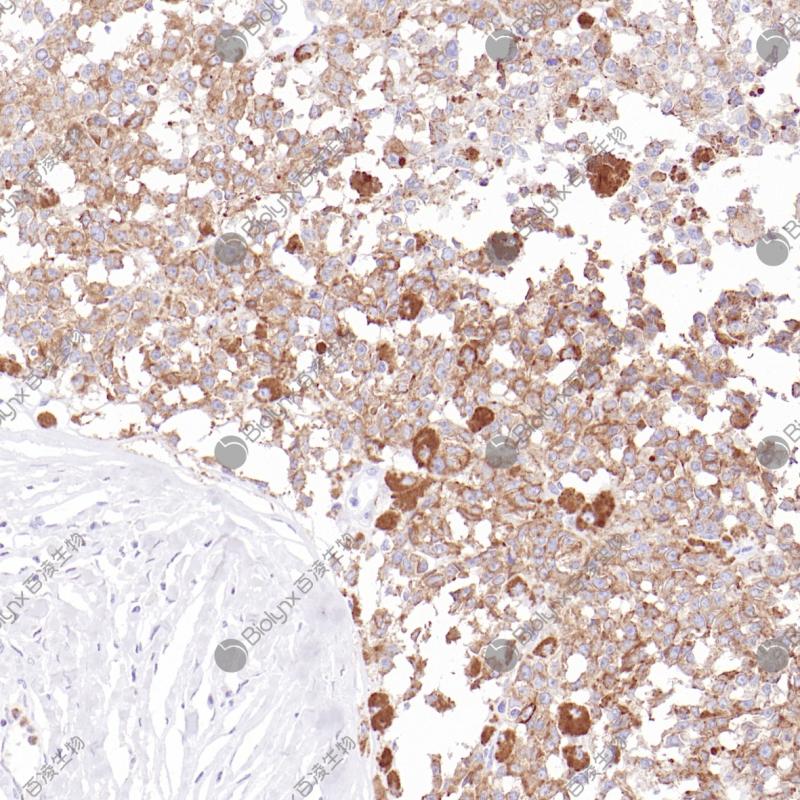

胰腺导管癌 肿瘤细胞缺失表达部位SMAD4(BP6219)染色

SMAD 4与SMAD1和YY1在骨形态发生蛋白(BMP)介导的心脏特异性基因表达中起协同作用。它是在细胞核中形成的异质三聚体SMAD2-SMAD3-SMAD4复合物的组成部分,是TGF介导的信号通路所必需的,并促进SMAD2/SMAD4/FAST-1复合物与DNA的结合。SMAD 4在大多数组织中呈细胞质和核表达。SMAD 4基因的改变最初是在胰腺癌(导管腺癌)中发现的,但也出现在各种癌症中,如结直肠癌、胃癌、前列腺癌、黑色素瘤、头颈部癌和许多其他癌症中。

目录号

BX50242

克隆号

BP6219

阳性对照

胰腺导管癌

亚细胞定位

细胞核/细胞质